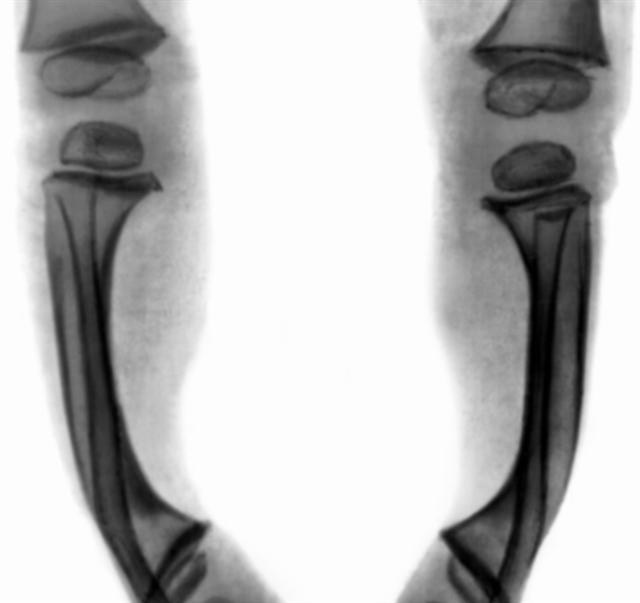

Рис. 7. Рентгенограмма нижних конечностей ребенка 1 года 4 месяцев: типичная рахитическая деформация большеберцовых костей.